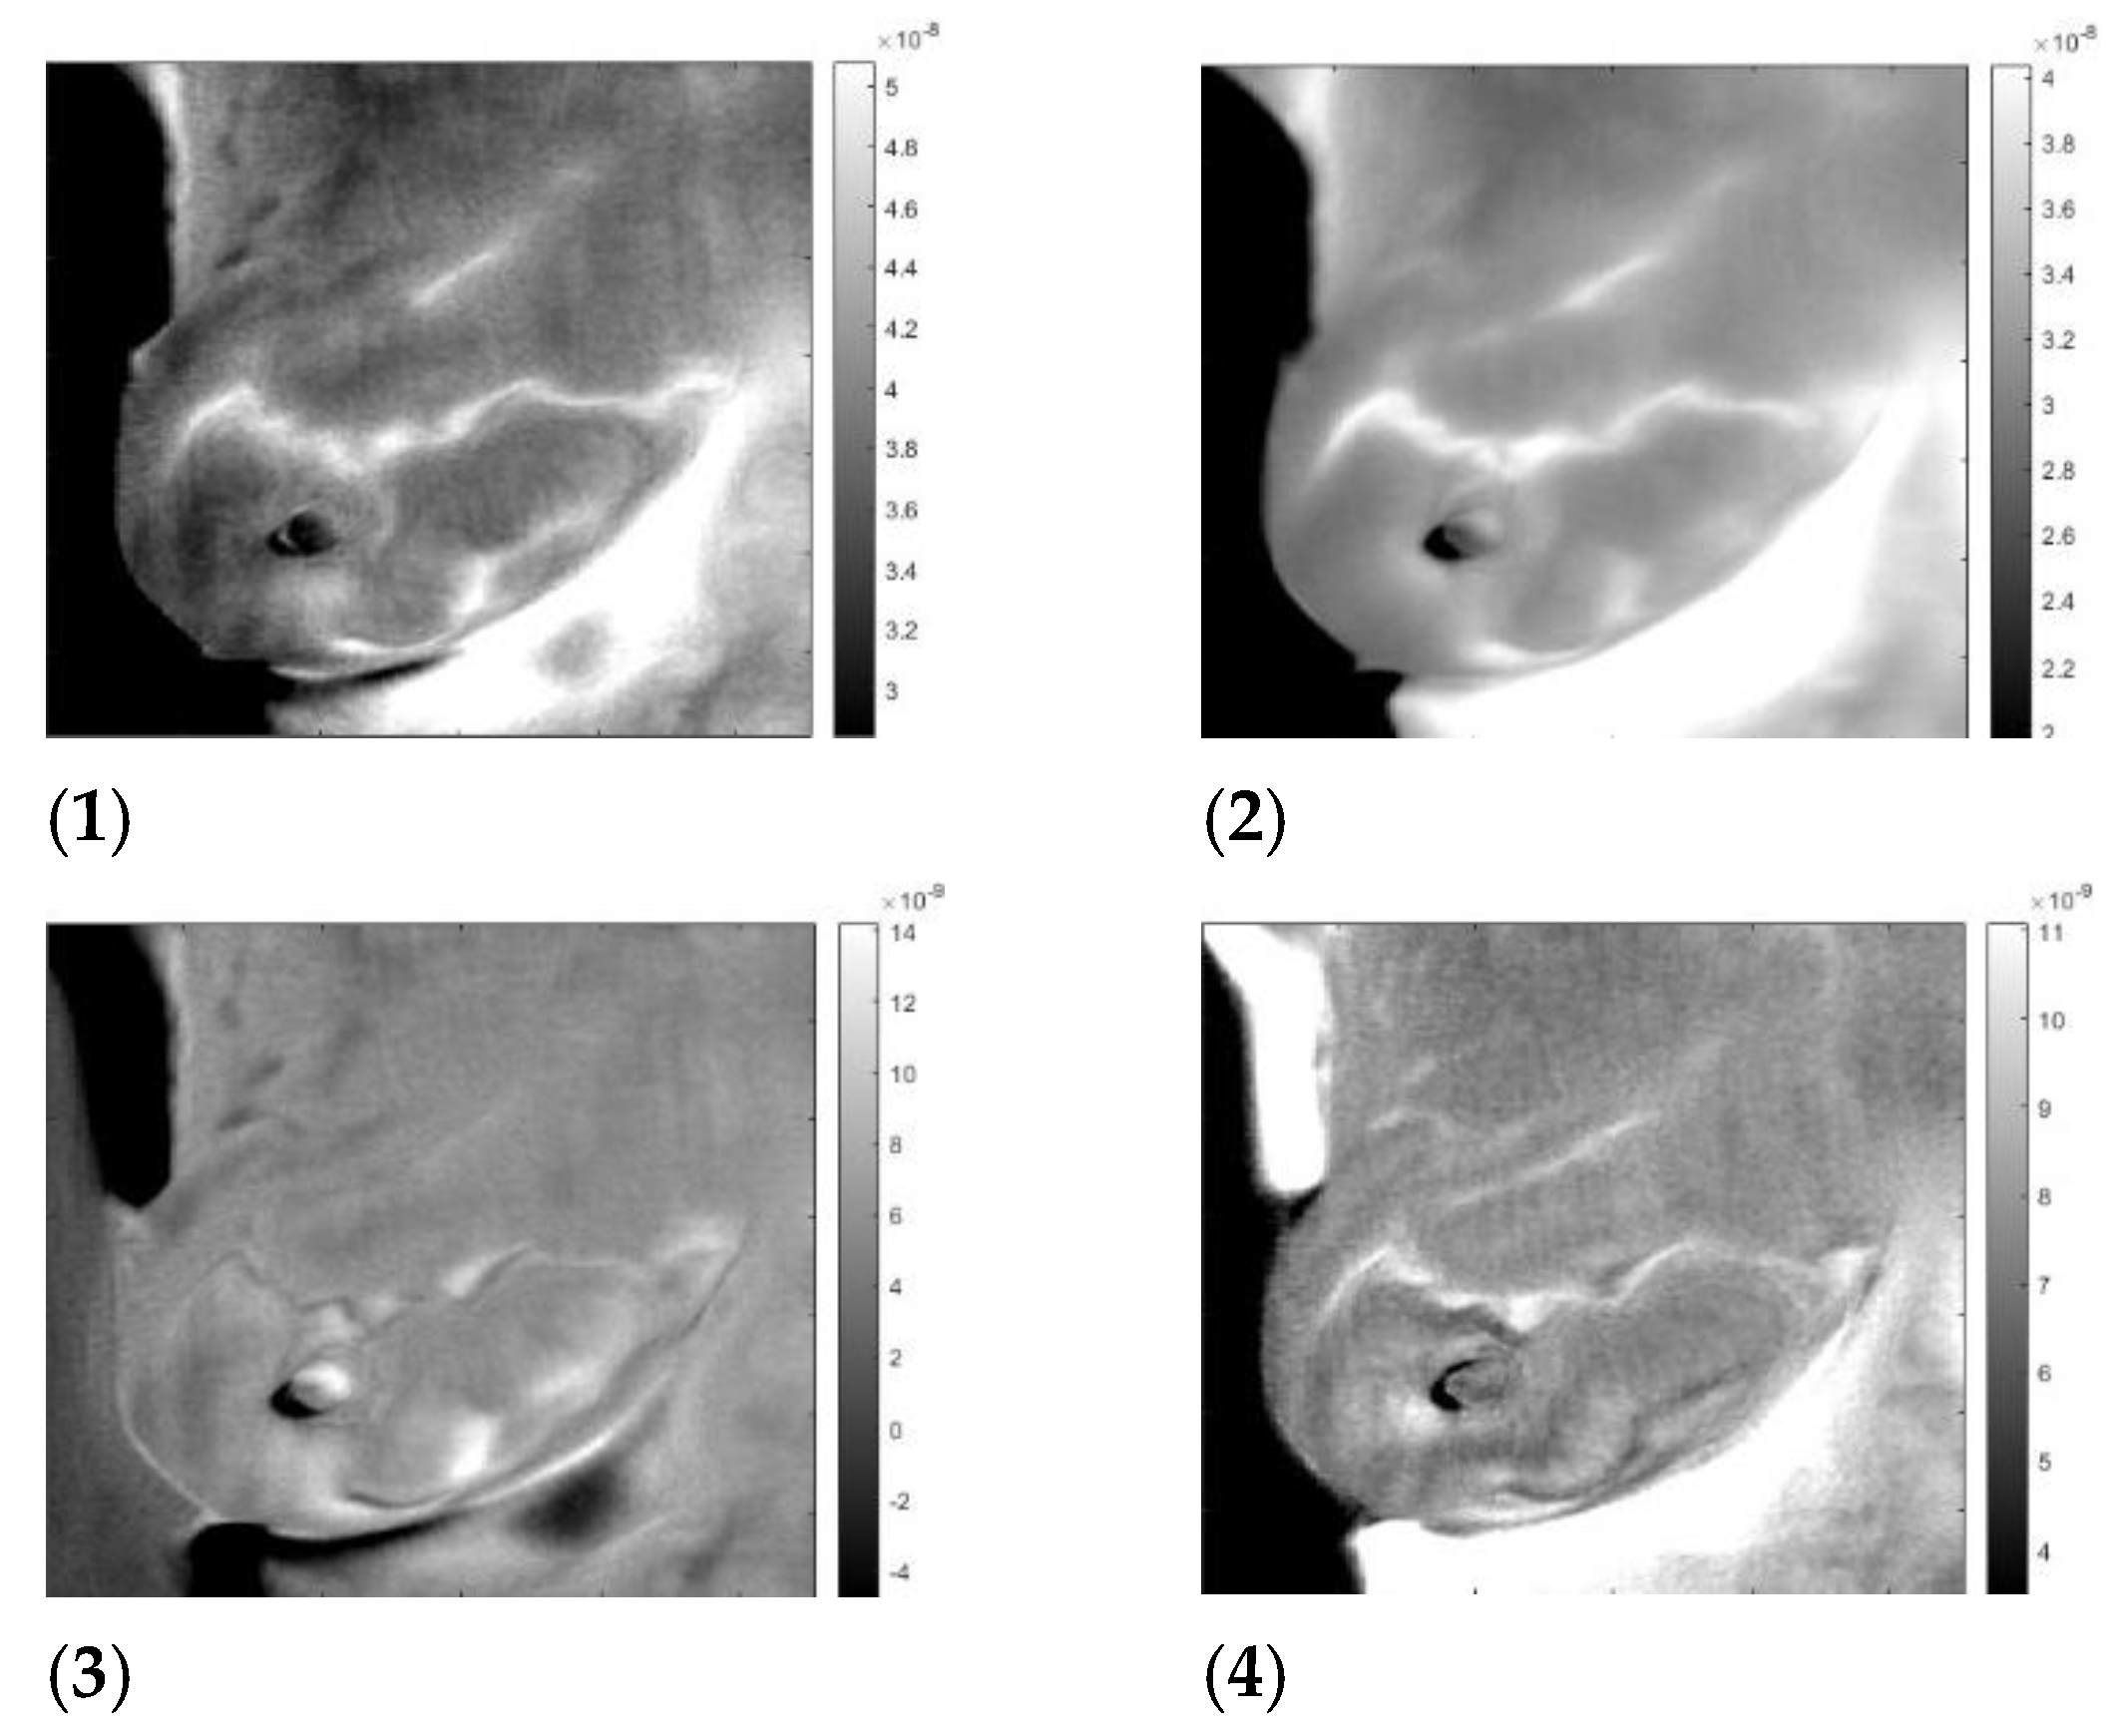

3. Results

3.3. Analysis